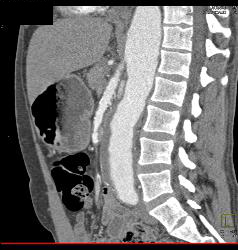

Superior Mesenteric Artery (SMA) Occlusion